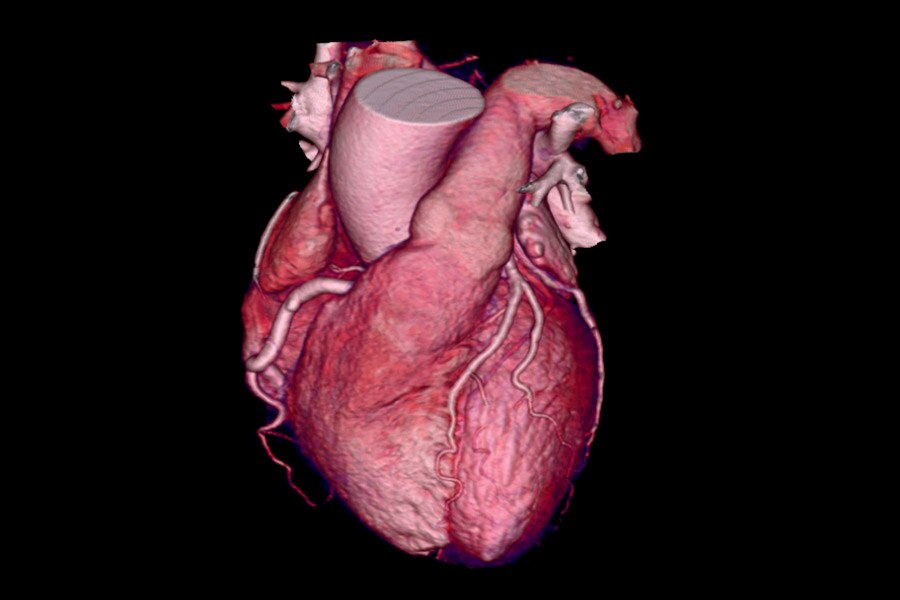

62-year-old female - 62 BPM, BMI 29